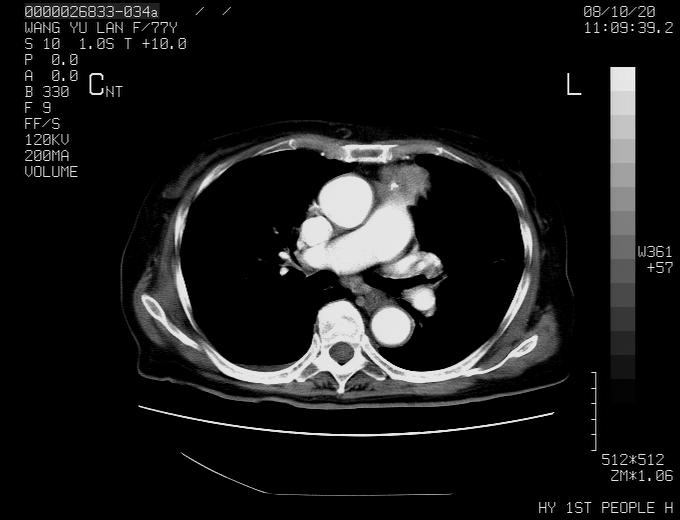

女性,77岁,胸部疼痛半月。左上肺团块影,本人考虑血管畸形,请分析

动脉期未见大血管同步强化,首先考虑周围型肺癌

动脉期病灶近中线侧可见星芒状与大血管同等强化密度,支持考虑血管畸形伴血栓形成,动脉期不曲型,不除外周围型肺癌

1、考虑avm可能性大。2、纵隔有肿大淋巴结,左肺上叶有炎性病变,不排除肺癌并转移可能。